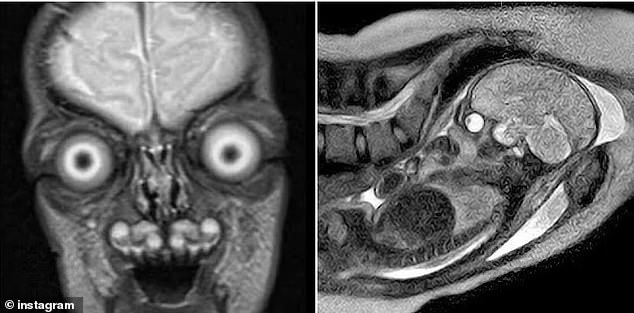

Disturbing images of fetal MRIs have once again ignited a firestorm of public concern, raising urgent questions about the safety and necessity of these scans during pregnancy. The stark, almost otherworldly visuals—showing a baby's skeleton as a ghostly white silhouette against dark tissue—have gone viral on social media, prompting debates about whether the medical value of these scans justifies the psychological toll on expectant mothers. But amid the unease, experts are urging clarity: these images, though haunting, are a critical tool in diagnosing complex fetal conditions.

The haunting clarity of MRI scans lies in their ability to reveal every detail of a developing fetus. Bones appear as bright, crystalline structures, while fluid-filled organs like the eyes form dark, cavernous voids that can seem almost alien. For mothers who encounter these images online, the effect is often unsettling. Yet, as one expectant mother put it, 'They look like a fossil trapped in a living body. But is the clarity worth the unease?' The answer, according to medical professionals, hinges on context: fetal MRIs are reserved for high-risk pregnancies where ultrasounds fail to provide sufficient detail.